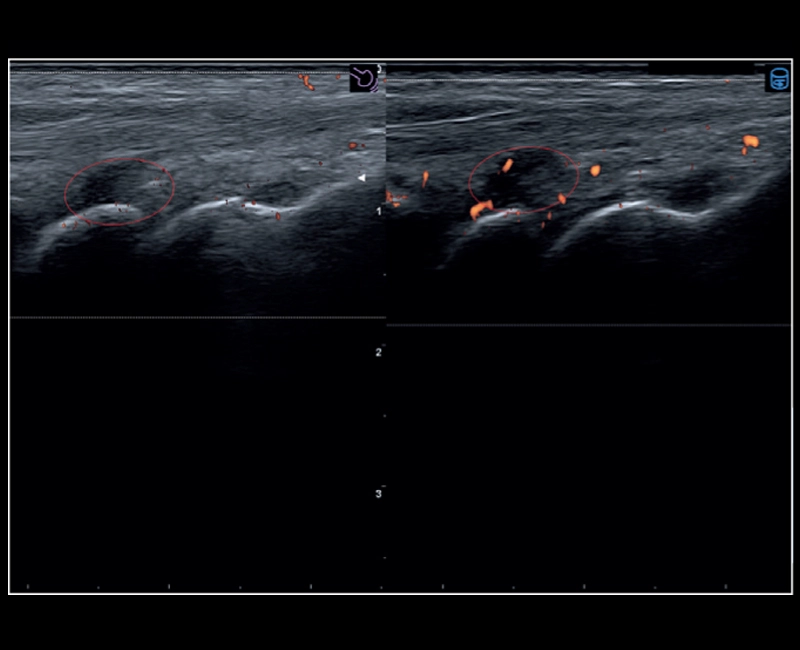

MyLab™9 Platform - Advanced hemodynamic analysis in thyroid nodule with microV

MyLab™9 Platform - Advanced hemodynamic analysis in thyroid nodule with microV